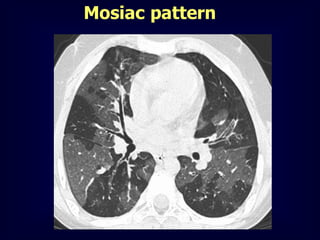

Mosiac pattern

Where is the pathology ???????

in the areas with increased density

meaning there is ground glass

in the areas with decreased density

meaning there is air trapping

Pathology in black areas